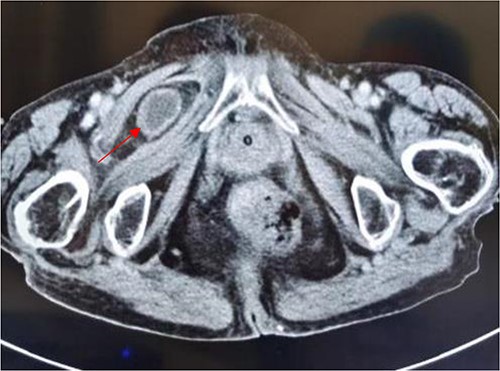

Sagittal view shows a right obturator hernia (indicated by red arrow).